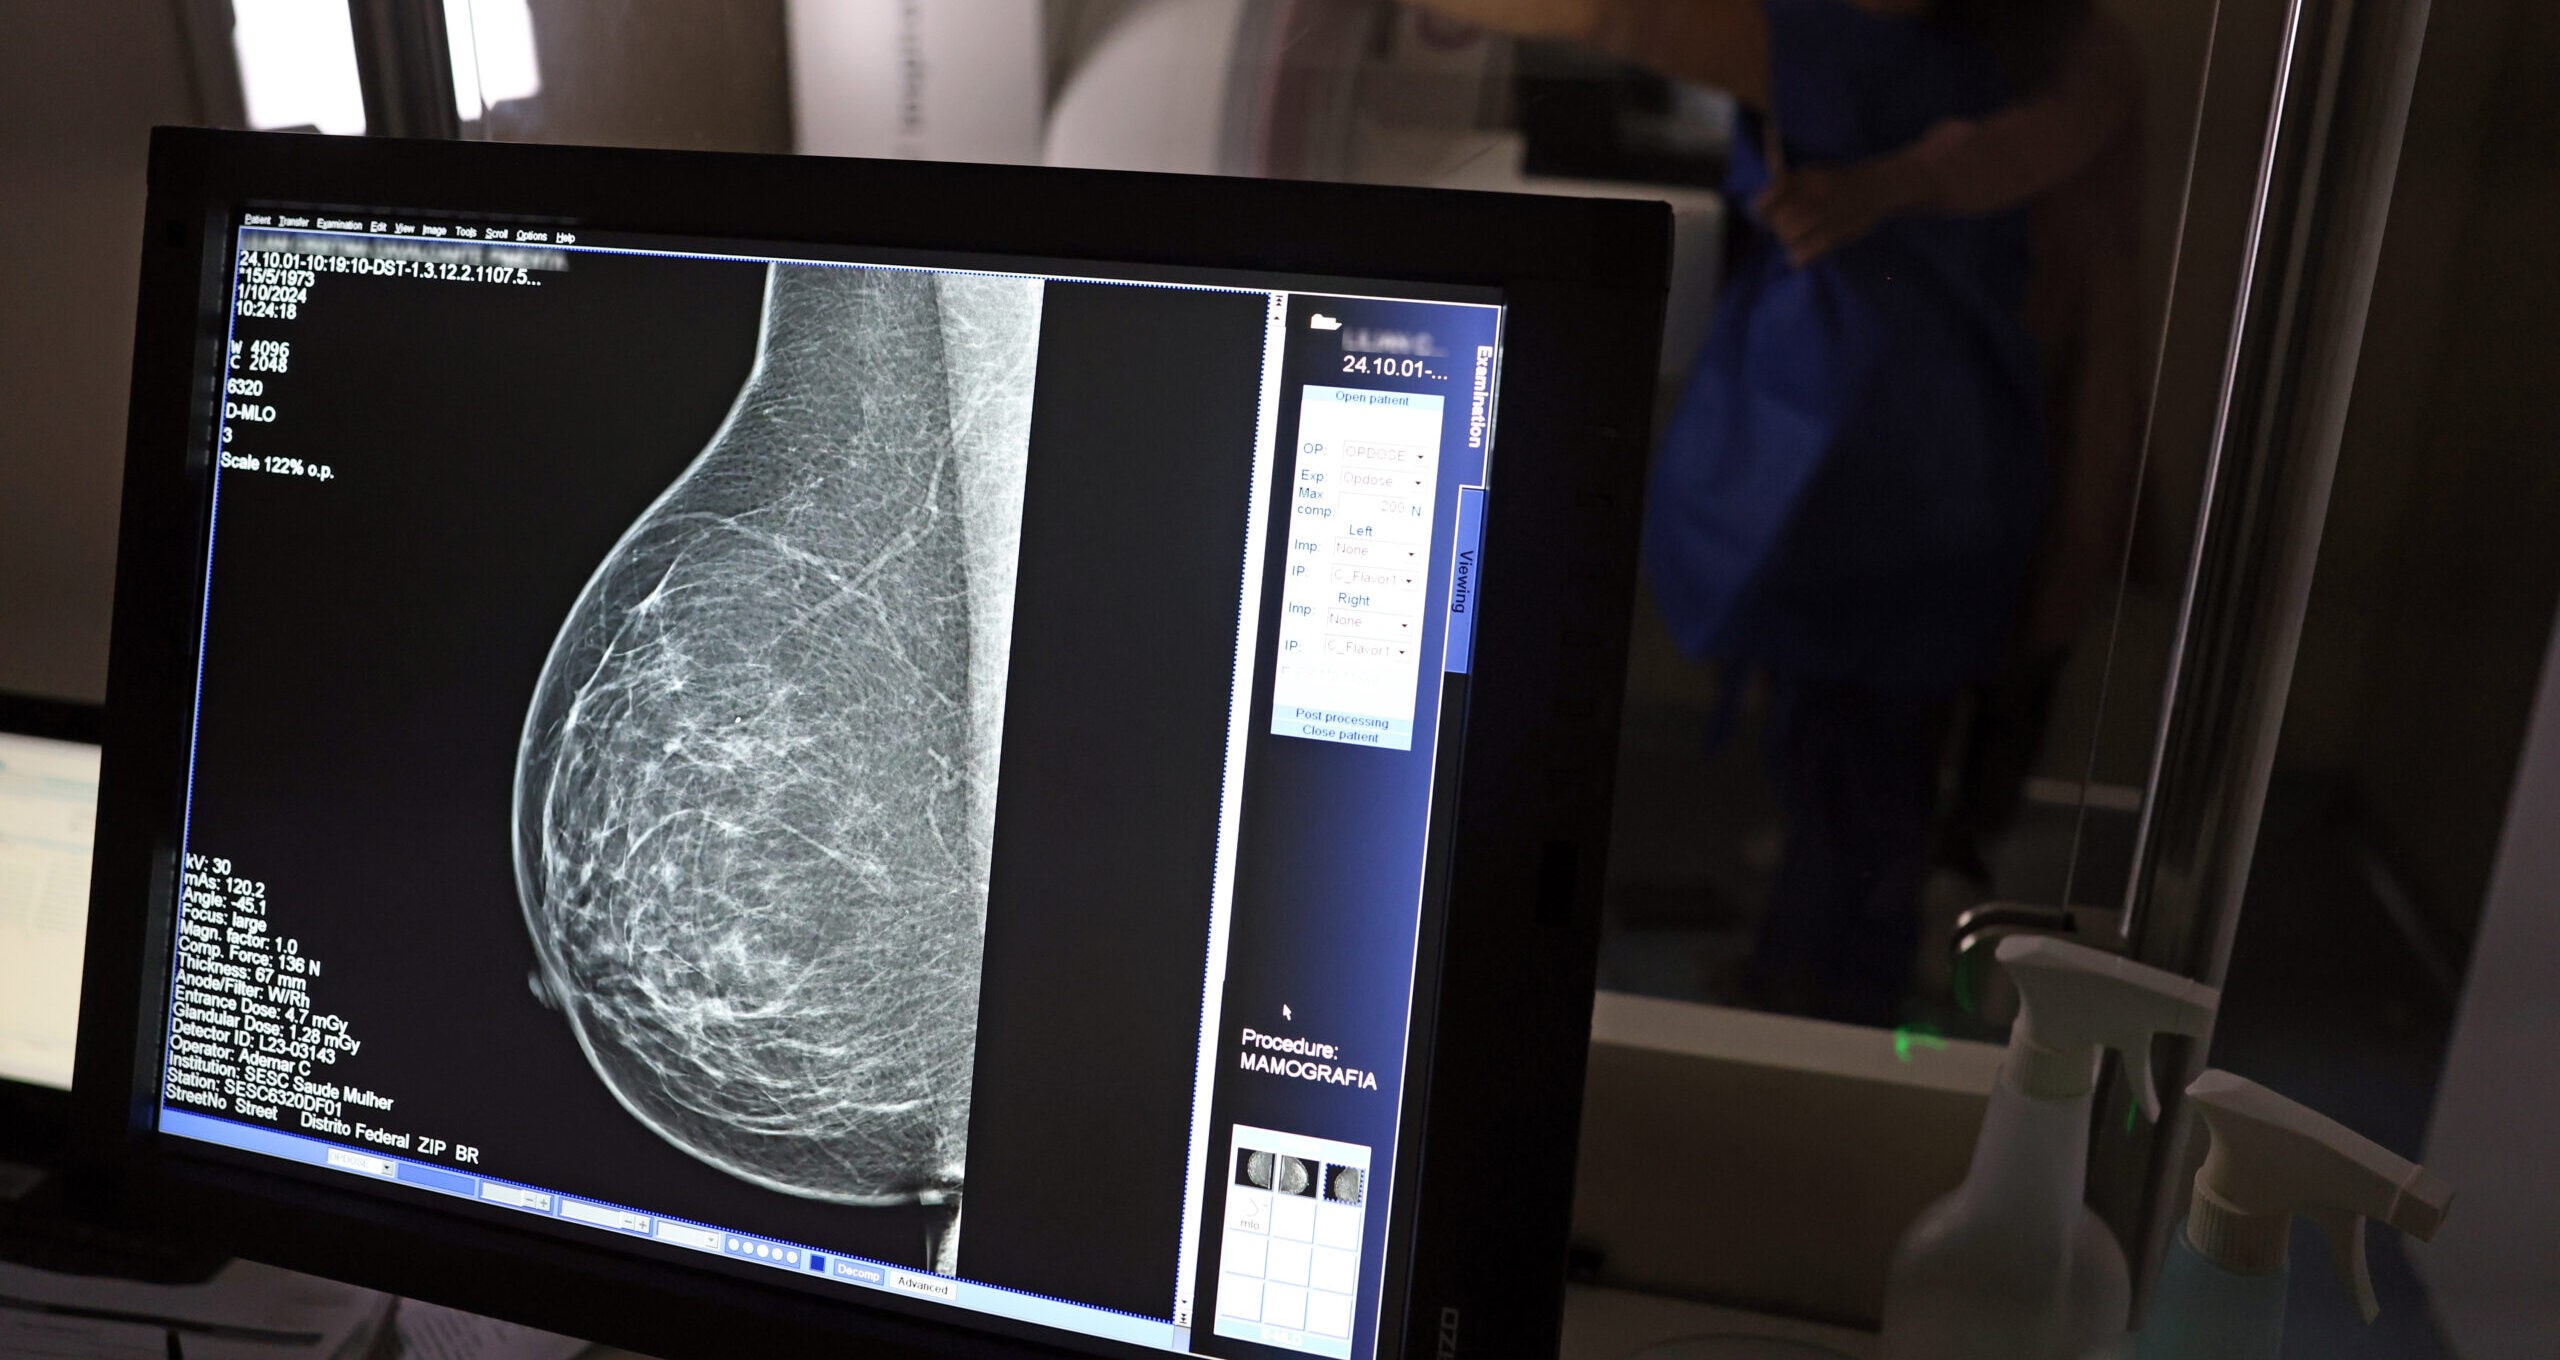

IA pode identificar calcificação de artérias por meio da mamografia.

A inteligência artificial pode ser utilizada para prever o risco de doenças cardiovasculares em mulheres a partir de análises de mamografias.

Segundo a pesquisa, a IA consegue avaliar o acúmulo de depósitos de cálcio nas artérias da mama a partir dos exames de raio-x, muito utilizados para o rastreamento de câncer.